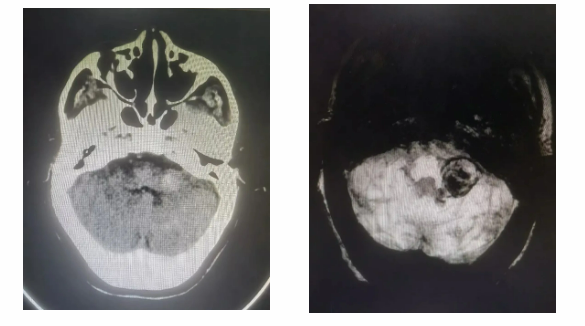

2020年,一次偶然检查,揭开了这场无声战役的序幕——七旬老人后颅窝发现不明占位,紧贴脑干,形如“刀尖起舞”。多家医院评估手术风险极高。当时老人家无身体不适,考虑手术风险高,一直随访观察。 直至今年2月,王奶奶出现了严重头痛,伴随着视力模糊和频繁呕吐。这些异常症状迅速引起了家人的警觉,紧急前往医院就诊。复查头颅MRI检查颅内占位较起初增大约3倍,约3✕4cm大小,外侧压迫后组颅神经舌咽致无法吞咽食物,压迫迷走神经致反复呕吐,内侧压迫脑干致无法行走。 面对如此严峻的情况,患者家属与医生多次深入沟通,最终决定在我院神经外科进行手术治疗。这是一场与时间赛跑的战斗,也是一次对医疗技术与团队协作的极大考验。

1、考虑后颅窝PICA(小脑后下动脉)巨大血栓性动脉瘤可能性大,同时不排除动脉瘤合并独立肿瘤可能,手术切口选择远外侧入路,充分显露左侧后颅窝;

3、术前完善脑血管造影,了解颅内血管状态。术前造影发现左侧小脑后下动脉P3段动脉瘤动脉瘤,进步证实血栓性动脉瘤可能。